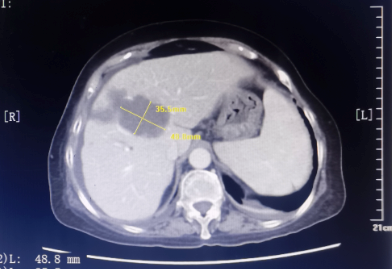

患者为67岁女性,1年余前诊断胃腺癌晚期,肝脏、骨骼及淋巴结多发转移,本次入院复查发现肝脏病灶进展,科主任白俊主任医师、主管医生刘莹主治医师详细分析并与患者家属沟通病情,考虑患者既往接受多线系统性抗肿瘤药物治疗,且治疗过程中多次出现剂量限制性骨髓毒性,继续更换药物治疗的选择空间不多,推荐超声引导下微波消融部分肝脏转移病灶,以期为后续继续免疫及靶向治疗创造在体瘤苗的机会。段宝军副主任医师认真阅片后,考虑该例患者肝转移病灶大(最大径超过5厘米),且毗邻膈肌、肝左静脉及第一肝门等重要结构,因此采用3D可视化手术规划系统设计微波消融方案,在麻醉科常建华副主任医师及手术室的精心配合下,顺利完成了肝转移病灶微波消融手术。

3D可视化系统可通过分析、融合、渲染等处理患者术前增强MRI或CT影像数据,在系统上创建不同的模块(如正常肝、病肝、门静脉、肝静脉等模块),对肝内外胆管及动、静脉系统重建,分析病灶与周围重要器官的关系,以及可能损伤的结构,确定安全边界,模拟进针路径、针数、消融时间,计算肿瘤体积、剩余肝体积,用不同颜色代表进针次序,对较大肿瘤需不断调整针的空间位置使热场范围能够覆盖安全边界。该技术辅助超声引导下肝癌微波消融术可提高消融成功概率、有利于制定更加合理的手术方案,减少消融手术并发症的发生,为肝癌的精准、安全消融治疗提供了新的选择。